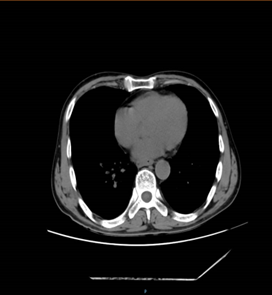

患者情況 + + + + 患者楊先生,57歲,既往肺結(jié)核病史,因2+月前因“吞咽困難”未予重視,出現(xiàn)進(jìn)食后嘔吐,嘔吐物為胃內(nèi)容物,近3月來體重下降約“10kg”,就診于外院,胃鏡提示食管占位鱗狀上皮重度異性增生,于2024年7月29日以“食管占位”收入我科繼續(xù)治療,頸部增強(qiáng)

CT提示食管下段鱗癌。結(jié)合患者既往肺結(jié)核病史肺功能及身體情況差。 術(shù)前相關(guān)影像學(xué)檢查 術(shù)前詳細(xì)討論,做好充分準(zhǔn)備 + + + + 術(shù)前,徐靜峰主任邀請(qǐng)麻醉科、腫瘤科、結(jié)核科以及輸血科等多個(gè)學(xué)科的專家進(jìn)行深入討論,一致決定為患者執(zhí)行一項(xiàng)頸胸腹三切口食管癌根治術(shù)。這是一次技術(shù)要求極高的四級(jí)手術(shù),術(shù)前準(zhǔn)備工作不僅包括精確的影像學(xué)和病理學(xué)評(píng)估,還必須應(yīng)對(duì)患者所面臨的多種基礎(chǔ)疾病和潛在并發(fā)癥的挑戰(zhàn)。 手術(shù)圓滿成功,彰顯團(tuán)隊(duì)實(shí)力 8月20日,徐靜峰主任團(tuán)隊(duì)在麻醉科和手術(shù)室的完美協(xié)作下,成功為楊先生在全身麻醉狀態(tài)下執(zhí)行了胸腹腔鏡聯(lián)合頸胸腹三切口食管癌根治術(shù)。手術(shù)過程中,麻醉順利進(jìn)行,手術(shù)也順利完成,術(shù)中出血量控制在約50毫升,達(dá)到了預(yù)期的理想效果。這次手術(shù)不僅彰顯了我院胸外科技術(shù)的進(jìn)一步提升,也展示了徐靜峰主任團(tuán)隊(duì)在食管癌治療領(lǐng)域的精湛技藝、細(xì)致護(hù)理,以及各科室之間卓越的協(xié)作能力。 術(shù)后精心護(hù)理,攻克疑難病癥 患者護(hù)理團(tuán)隊(duì)通過十二指腸營(yíng)養(yǎng)管為患者提供腸內(nèi)營(yíng)養(yǎng),注入流質(zhì)飲食。他們強(qiáng)化了對(duì)呼吸道、胃腸道、傷口及引流的管理,并進(jìn)行了細(xì)致的護(hù)理觀察。術(shù)后第二天,患者便能夠下床活動(dòng),到了第七天,患者已能正常經(jīng)口攝入流質(zhì)飲食。在二十天后,患者順利出院,期間未出現(xiàn)任何術(shù)后并發(fā)癥。這一過程表現(xiàn)出創(chuàng)傷小、風(fēng)險(xiǎn)低、出血少以及預(yù)后優(yōu)良的特點(diǎn)。 市公衛(wèi)中心胸外科團(tuán)隊(duì)將持續(xù)以患者為核心,提供卓越的醫(yī)療技術(shù)和一流的??谱o(hù)理服務(wù),攻克更多復(fù)雜病癥,為廣大的患者群體帶來新的希望。 胸外科小科普: ? 食管是將食物從口腔傳輸?shù)轿覆康墓艿馈?/p> 食管癌又叫食道癌好發(fā)于食管內(nèi)壁的上皮細(xì)胞,是作為世界常見的惡性腫瘤之一,全球約有40萬新發(fā)病例,約30萬人死于食管癌,中國(guó)是世界上食管癌發(fā)病率最高的地區(qū)之一,一般男性高于女性。 ? ? ? 發(fā)生食管癌的臨床表現(xiàn): 早期:1、梗咽感 2、胸骨后灼感 3、異物感 4、無癥狀; 進(jìn)展期:1、進(jìn)行性吞咽困難 2、嘔吐、3、后背疼痛 4、體重下降; 晚期:1、侵犯穿孔(疼痛、嗆咳、嘔血) 2、神經(jīng)受累(聲音嘶?。?3、消瘦、貧血、低蛋白 4、遠(yuǎn)處轉(zhuǎn)移。 什么情況會(huì)誘發(fā)食管癌:愛吃腌制食品、趁熱吃趁熱喝、煙酒不離手、遺傳因素。 在正常情況下,食管的耐受高溫在50-60,但對(duì)一般人來說,口腔覺得燙的時(shí)候,食物起碼是70左右了,超出了食管的承受能力。